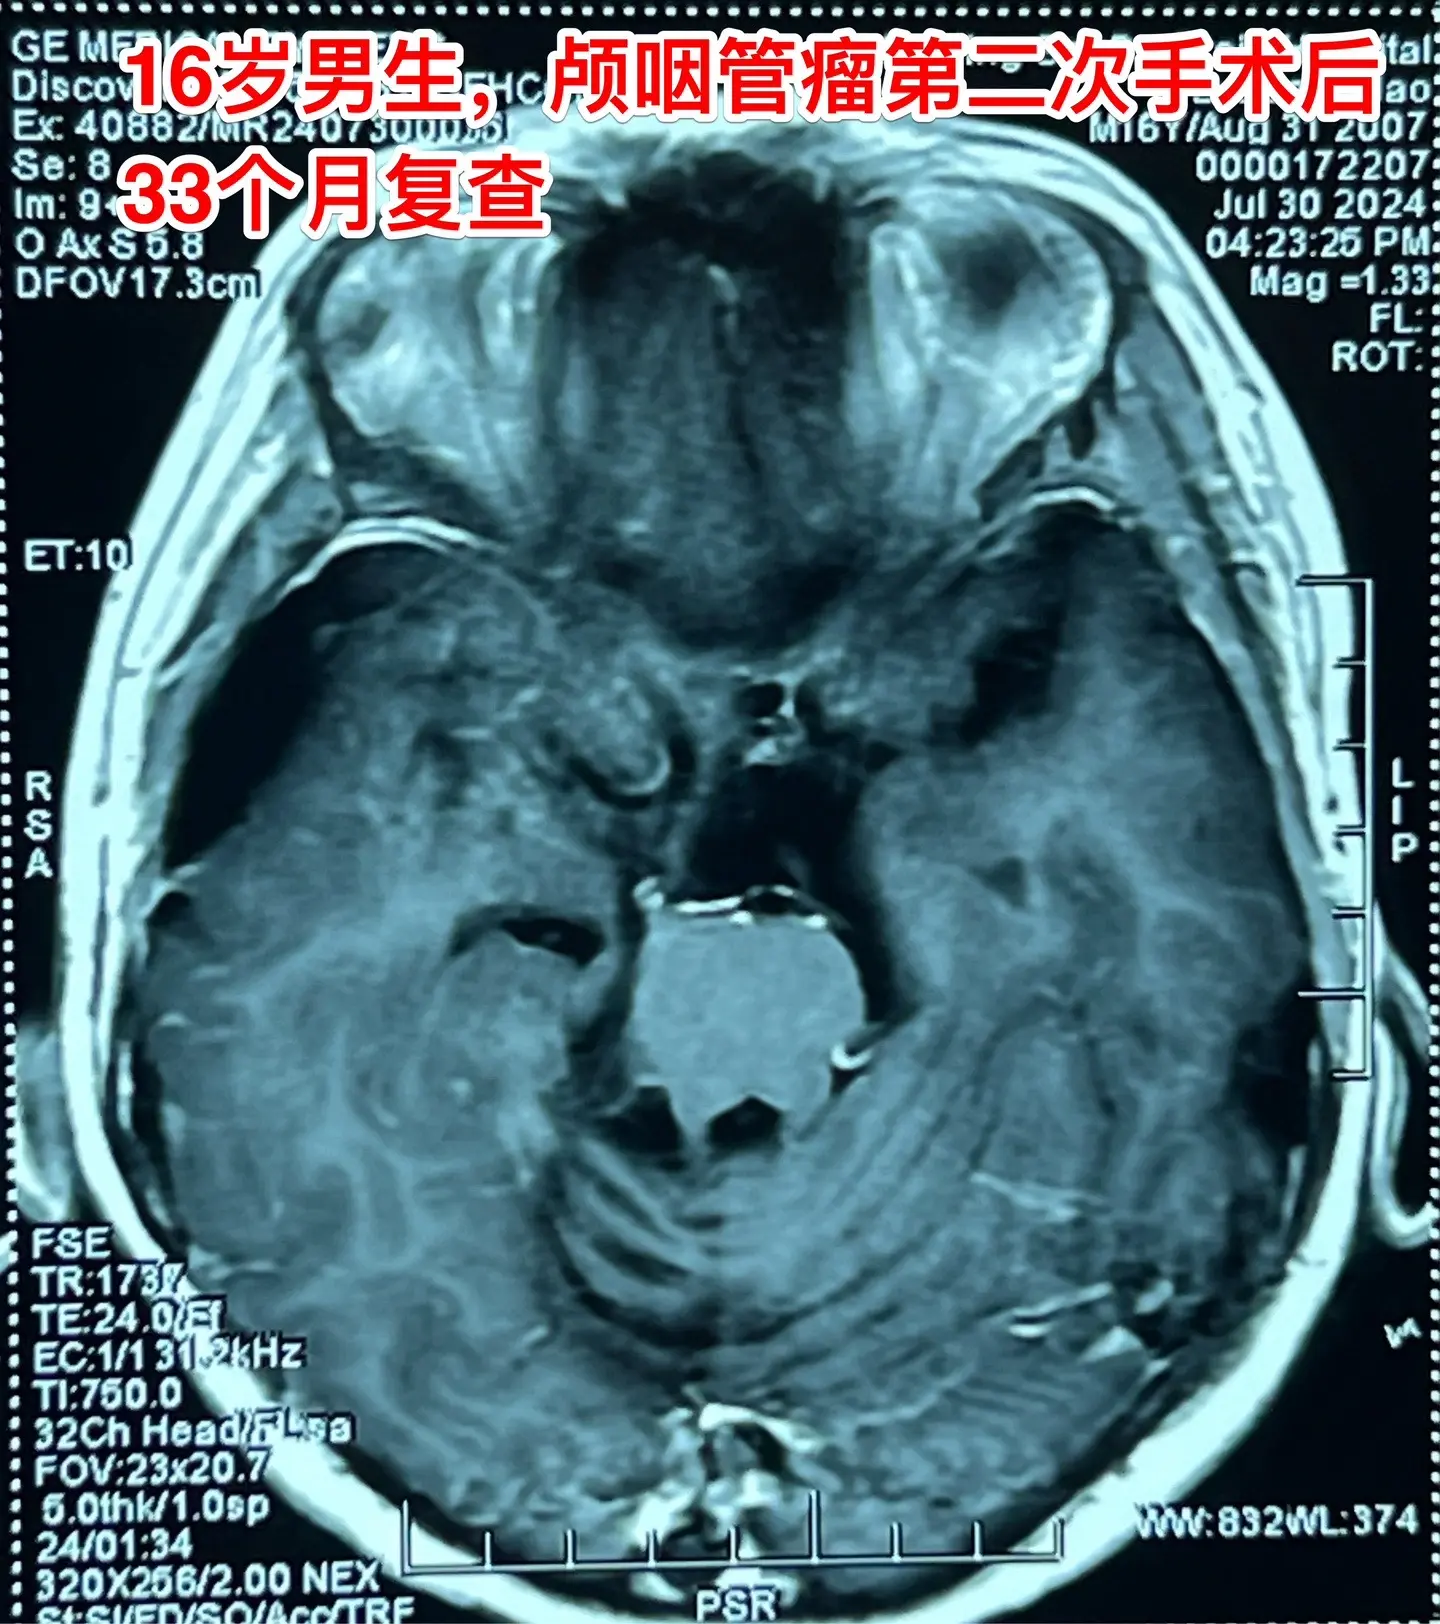

颅咽管瘤复发导致听力下降眼睑下垂。2024年7月30日 16岁男孩子颅咽管瘤第二次手术后33个月复查,患者妈妈带着三个孩子从昆明到北京复查,肿瘤没有复发,高高兴兴地回家去了。距离在外院的第一次手术已经八年了。 图7、图8是2021年10月手术前的CT,肿瘤形态很不规则,体积大,手术难度很大。 手术前患者右耳听力障碍、右眼睑下垂,手术后患者右耳听力恢复,右侧眼睑下垂症状恢复正常,能正常上学读书。家长对手术效果很满意。 希望肿瘤永远不复发。